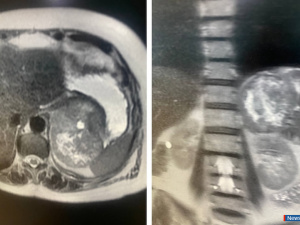

В преддверии Нового года врачи-онкологи миасской Городской больницы № 2 провели уникальную операцию 64-летней пациентке, удалив 8-сантиметровую опухоль, которая распространялась в забрюшинное пространство и произрастала из стенки желудка. Подобные случаи встречаются крайне редко - около 10-15 случаев на миллион человек, отметили в пресс-службе медицинского учреждения.

Пациентка обратилась к врачам после нескольких месяцев болей в животе. Первоначальное обследование в поликлинике выявило опухоль неясного генеза. Компьютерная томография подтвердила наличие объемного образования, и женщину направили в отделение абдоминальной онкологии для уточнения диагноза и проведения хирургического лечения.

Дополнительные исследования, включая МРТ и ФГС, показали, что опухоль не затрагивает просвет желудка, а располагается на его наружной стенке. Это позволило врачам предположить, что пациентка столкнулась с редкой формой саркомы желудка, требующей незамедлительного хирургического вмешательства.

Операция, которую провели заместитель главного врача Алексей Зайков и врач-онколог Геннадий Калашников, длилась полтора часа. Опухоль находилась между жизненно важными органами: желудком, поджелудочной железой, селезенкой, почкой, надпочечником и аортой. Она также инвазировала в диафрагму, что потребовало её частичной резекции. Врачам удалось полностью освободить опухоль и удалить её вместе с частью стенки желудка, не вскрывая органа.

"Это кистозно-солидная опухоль забрюшинного пространства, она имеет в своем составе тканевой компонент и жидкость. Такое новообразование нельзя верифицировать, невозможно взять биопсию до удаления. Скорее всего, это агрессивная форма саркомы, медлить с операцией было нельзя", - рассказал заместитель главного врача по медицинской части, врач-онколог Алексей Зайков.